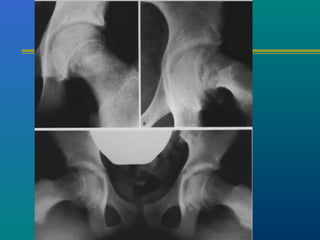

SLIPPED CAPITALSLIPPED CAPITAL

FEMORAL EPIPHYSISFEMORAL EPIPHYSIS

A true adolescent problem

Gradual or acute slip

through the capital

femoral physis

Boys more than girls

Left more than right

Bilateral – 20 %

Investigations

X-ray – AP

Frog leg lateral view

( contraindicated when

suspecting acute slip)

Goal of treatment

 Promote early physeal closure

 Prevent additional slipping

 Relieve pain

 Correct deformity

 Restore function of hip

 Prevent complications